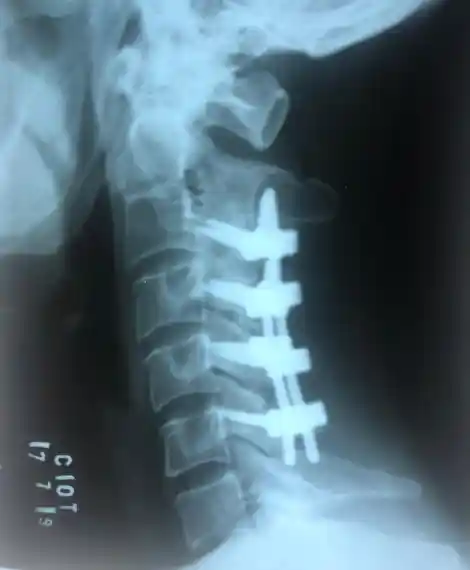

Durante o procedimento, utilizamos enxertos ósseos e implantes metálicos (parafusos, hastes e placas) para criar uma estrutura sólida e estável. Com o tempo, o osso cresce e se funde naturalmente, formando uma única estrutura óssea contínua.

Artrodese Cervical

Fusão das vértebras cervicais para tratar hérnia cervical, mielopatia, instabilidade e deformidades da região do pescoço.

• ACDF (Discectomia e Fusão Cervical Anterior)

• Corpectomia cervical

• Fusão cervical posterior

• Preservação da mobilidade